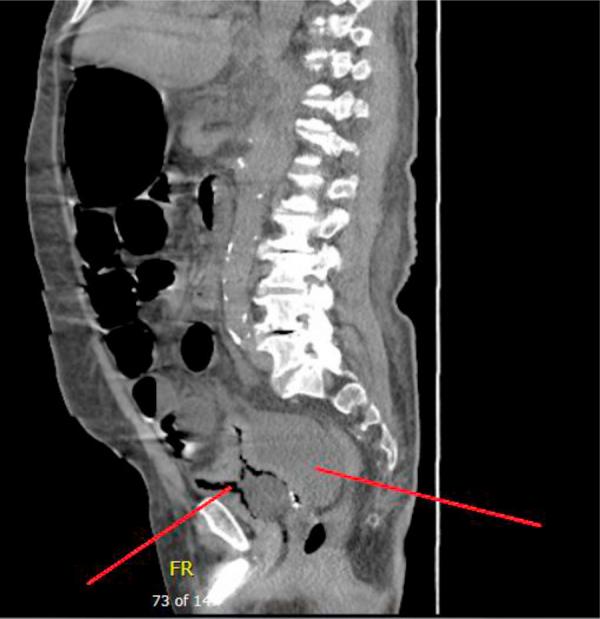

Spontaneous urinary bladder rupture is a rare urological emergency. It is usually secondary to an underlying pathology and it is an uncommon complication of urosepsis. We report a case of spontaneous urinary bladder rupture as a complication of urosepsis in a 67 year old male patient, who was admitted as a case of left diabetic foot and urinary tract infection.

A 67 year old male patient with a long standing indwelling urinary catheter and chronic cystitis developed acute peritonitis. Intraoperative finding was ruptured urinary bladder.

A few cases of spontaneous urinary bladder rupture due to infection were found in literature. The majority of the patients present with diffuse abdominal pain, and tenderness due to chemical peritonitis. In the majority of cases the bladder perforation was diagnosed intra-operative.

自发性膀胱破裂是一种罕见的泌尿外科急症。它通常继发于潜在的病理状况,是泌尿道感染的一种罕见并发症。我们报告一例67岁男性患者,因糖尿病足和尿路感染入院,其自发性膀胱破裂作为泌尿道感染的并发症。

一名67岁男性患者,长期留置导尿管且患有慢性膀胱炎,发生了急性腹膜炎。术中发现膀胱破裂。

文献中发现了一些因感染导致的自发性膀胱破裂病例。大多数患者表现为弥漫性腹痛以及化学性腹膜炎引起的压痛。在大多数病例中,膀胱穿孔是在术中诊断出来的。